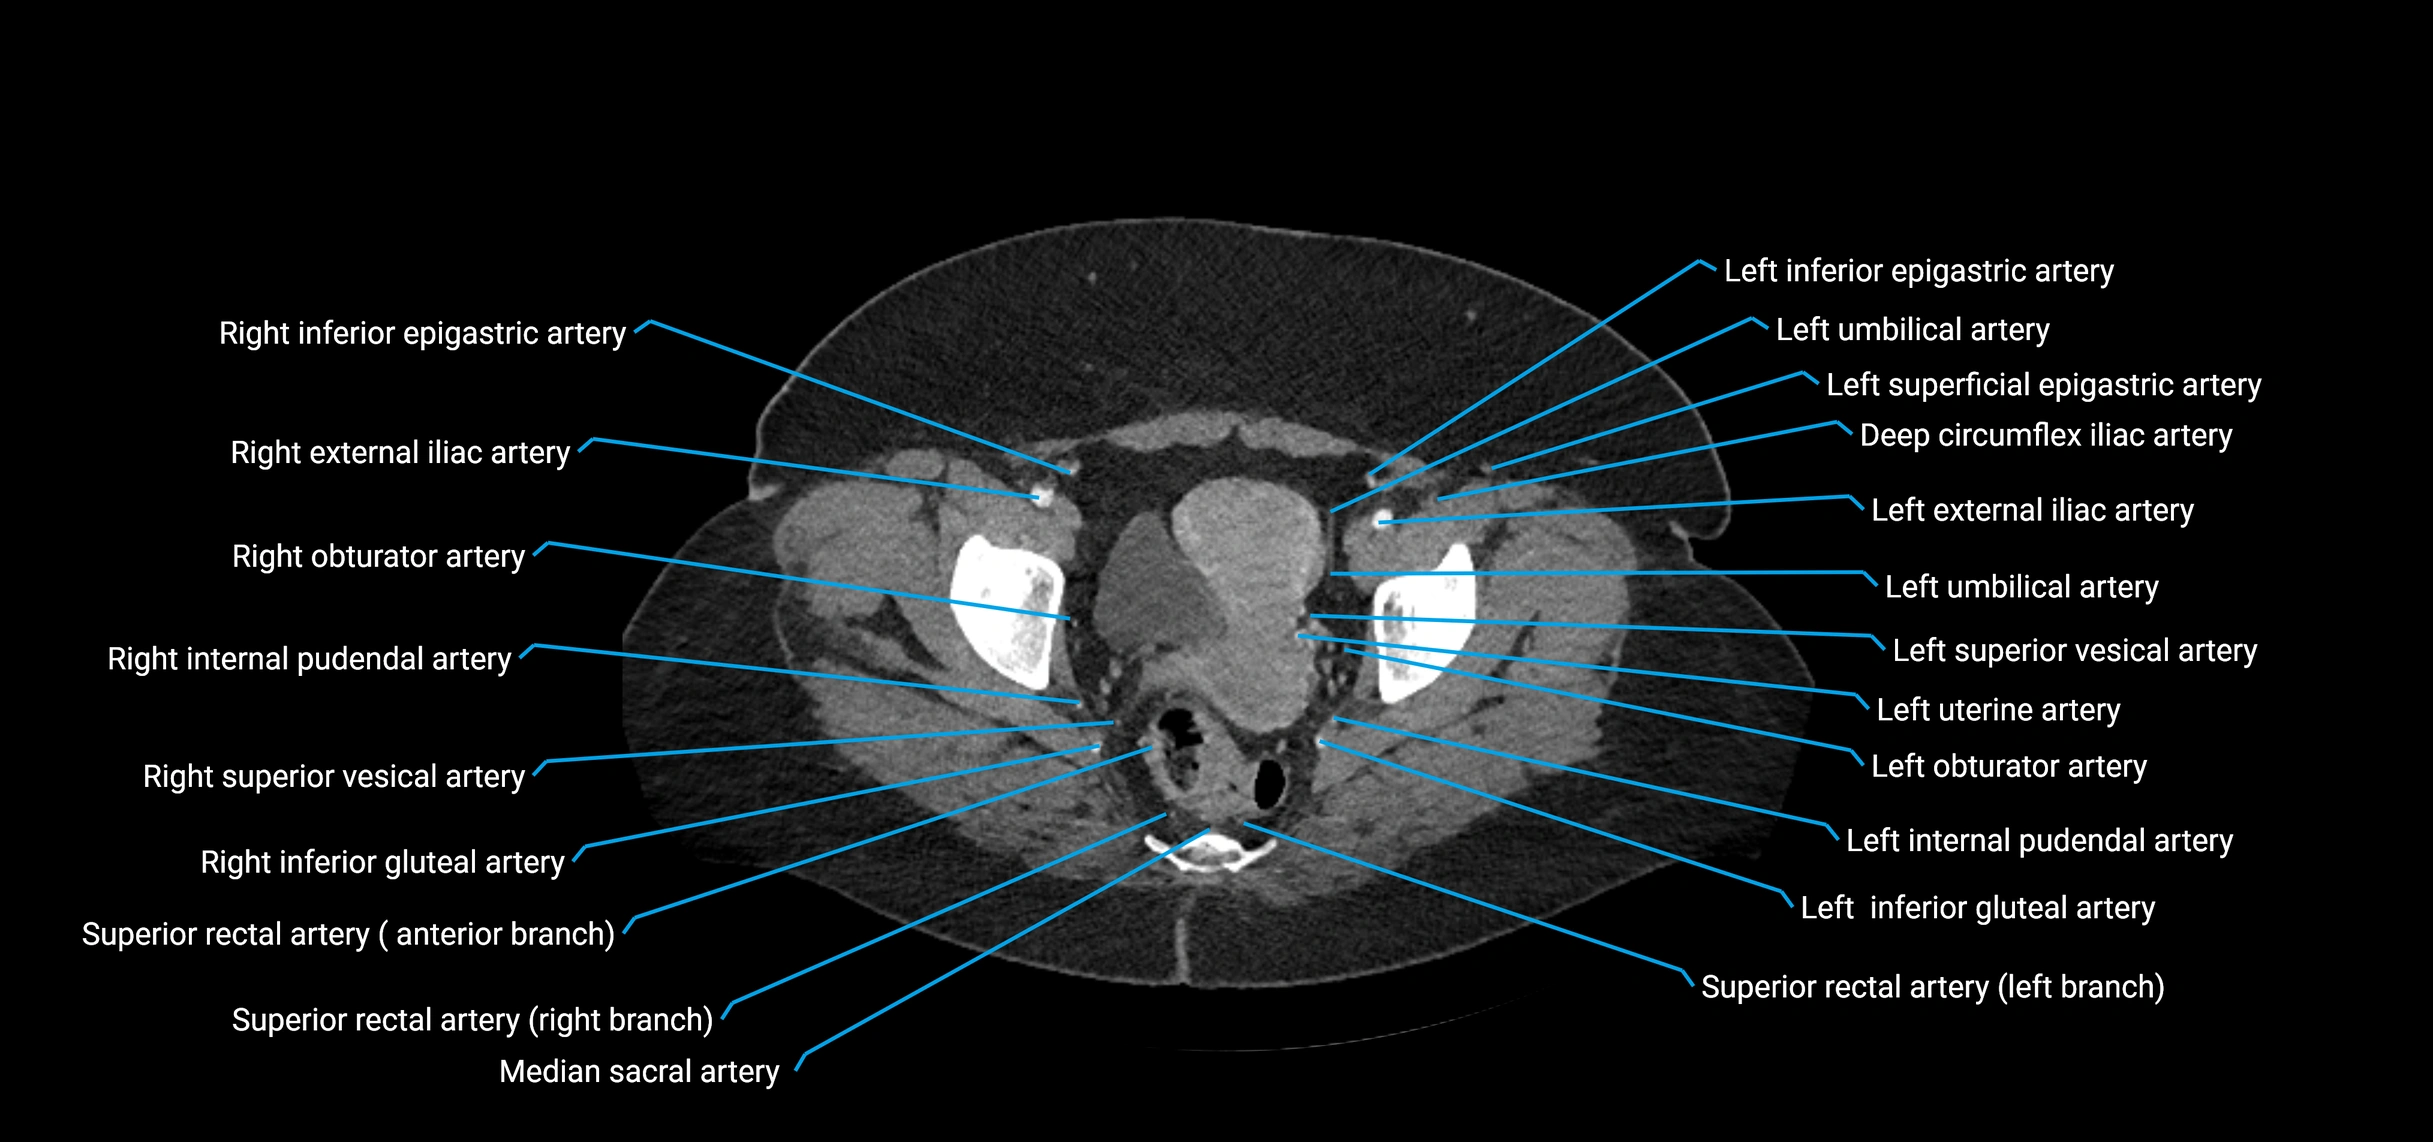

Contrast-enhanced CT (CTA):

• Gold standard for abdominal aortic imaging

• Provides excellent detail of lumen, wall, aneurysm, thrombus, and branch vessels

• Multiplanar and 3D reconstructions help in aneurysm measurement, stent graft planning, and dissection evaluation

• Detects acute rupture, traumatic injury, or occlusion with high sensitivity